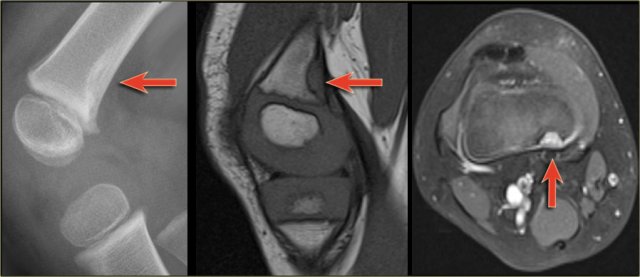

ABC (4)

On the left images of an aneurysmal or expansile well-defined osteolytic bone lesion in the proximal phalanx.

Notice the expansion and the enhancing rim.